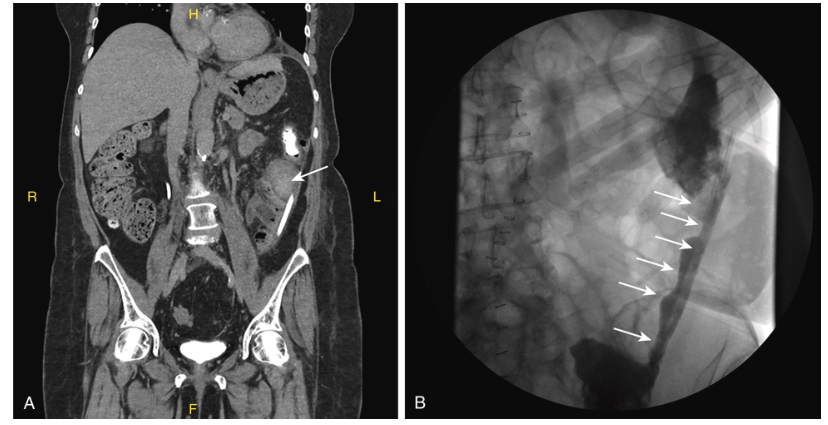

Diagnosis

Primary peritonitis is diagnosed by:

- Clinical suspicion in patient with ascites and signs of infection

- Paracentesis with ascitic fluid cell count ≥250 PMN/mm³

- Exclusion of a primary intraabdominal source of infection (clinical exam, imaging if needed)

- Positive ascitic fluid or blood culture